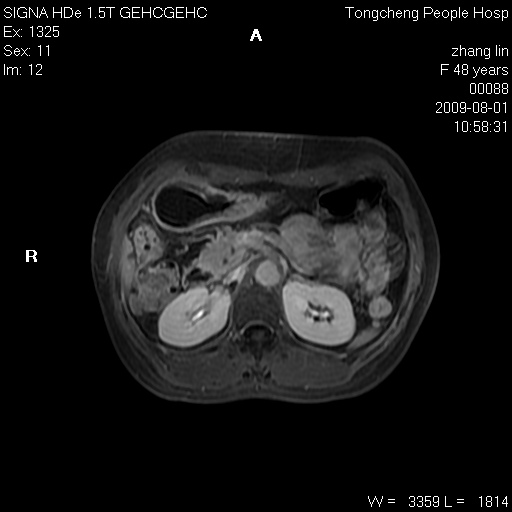

女,48岁。健康体检,彩超发现右肾占位性病变。平素健康。

临床诊断:右肾占位性病变,性质待定(囊肿?肿瘤?)。

上中腹部mr平扫+增强扫描,图像如下:

右肾上极见一类圆形病灶,t1wi呈等信号t2wi呈等高混杂信号,三期增强无强化,边界清---考虑囊肿出血。

同反相位均表现为等信号,病变无强化,考虑含蛋白的囊肿可能,弥散加权相或许有些帮助,